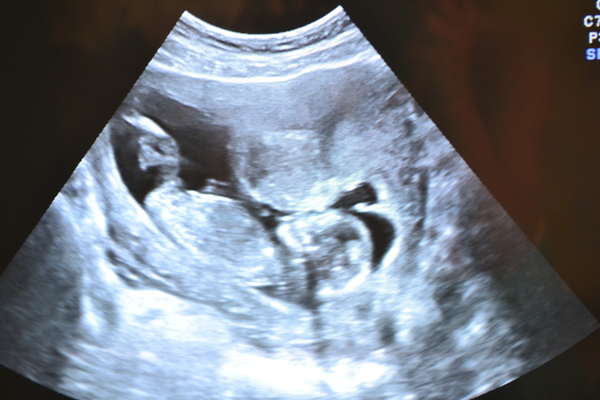

Результаты: УЗИ, КТГ, доплера, скринингаНу вот и мы сходили на первое наше контрольное УЗИ))Врач сказал что малыш развивается согласно сроку,(13 НЕДЕЛЬ И 5 ДНЕЙ), и все у него в норме)))На 55% пророчит мальчика,с нетеерпением буду ждать второе узи))))))Фото моего крошки под катом)